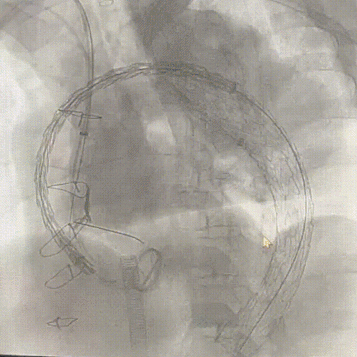

6. 造影提示左颈总血流稍差,使用双球囊同时扩张左颈总和左锁骨下动脉左颈总动脉再植入裸支架COOKZFV6-125-10-6.0血管支架。

双球囊同时扩充

7. 进行最终造影,支架形态良好,弓上三根分支血管显影通畅,腹主段造影显示内脏区分支显影良好,结束手术。

主动脉弓最终造影

腹主段最终造影